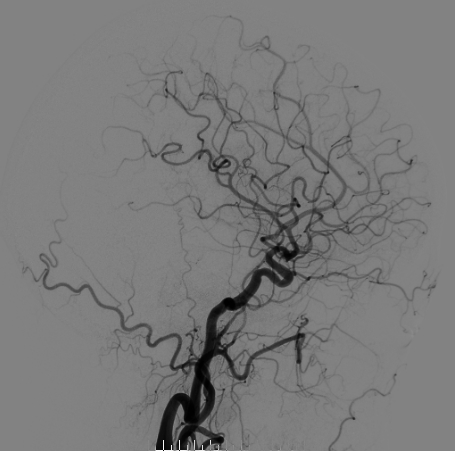

脑血管造影

左侧颈总造影

右侧颈总造影:右侧大脑中动脉瘤

右侧大脑中动脉瘤,瘤颈处发出颞支,颈宽3.79mm,瘤高3.51mm,远近端载瘤动脉直径分别为2.43mm、2.52mm。